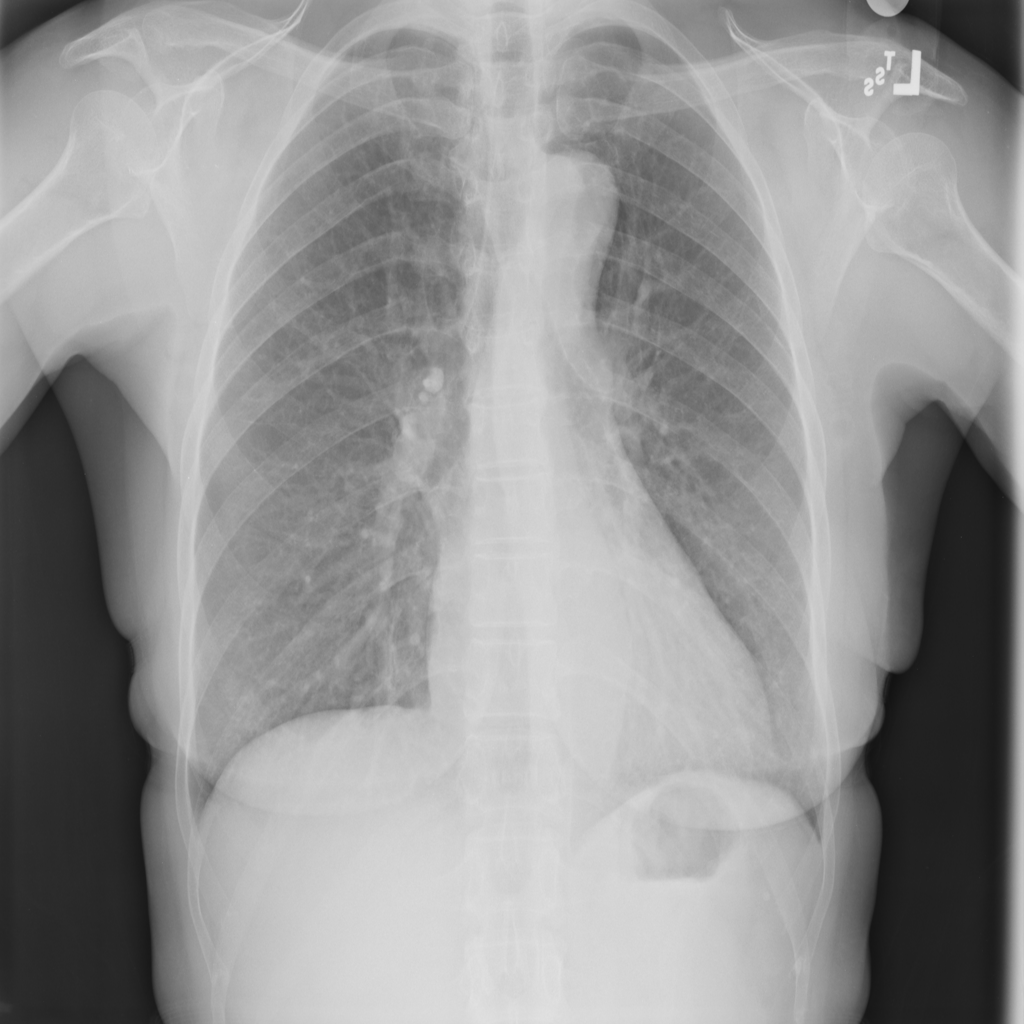

Showing up to 90 reference images for Nodule.

PAT-FB8F · IMG-000Nodule

PAT-FB8F · IMG-000

PA